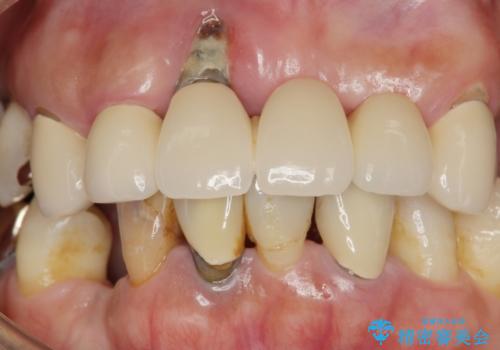

歯周病 全顎治療

- 前歯の見た目、入れ歯による噛めないことの改善を求めて来院されました。

検査により全顎的な歯周病治療、欠損のインプラント補綴、根管治療が必要な状態であることをお伝えし、治療を計画します。